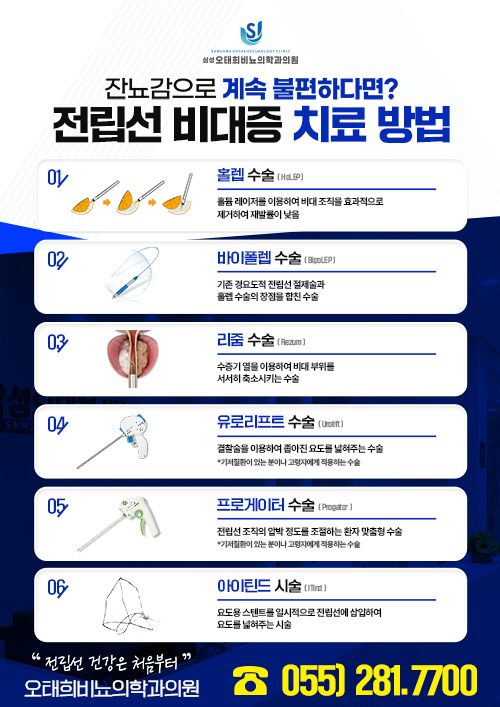

전립선

- 리줌(Rezum)

- 홀렙(HoLEP)

- 바이폴렙(BipoLEP)

- 유로리프트(Urolift)

- 프로게이터(Progator)

- 아이틴드(iTind)

- 전립선 비대증 치료 방법